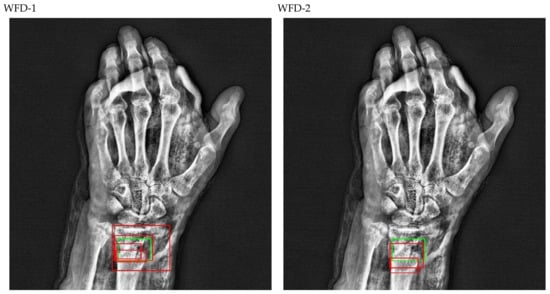

The bounding box outputs achieved from fracture detection performed with ensemble models in wrist X-ray images are provided in Figure 20 and Figure 21 below as a sample for the right/left hand in the dataset.

Figure 20.

Sample of right wrist fracture results [ground-truth bounding box (green), predicted bounding box (red)].

Figure 21.

Sample of left wrist fracture results [ground-truth bounding box (green), predicted bounding box (red)].

The predicted bounding boxes achieved fracture detection suggest that, as shown in the images in Figure 20 and Figure 21, the model that provides the most accurate results that are closest to the ground-truth bounding boxes is the WFD-C ensemble model developed in this study. Moreover, the examination of the number of predicted bounding boxes reveal that the model with the lowest number on the test data is also WFD-C. For the fracture detection in wrist X-ray images, Figure 22 below shows the total number of predicted bounding boxes obtained for each model on the test dataset as the result of the fracture detection performed with a total of 26 deep learning models, six of which are ensemble models.